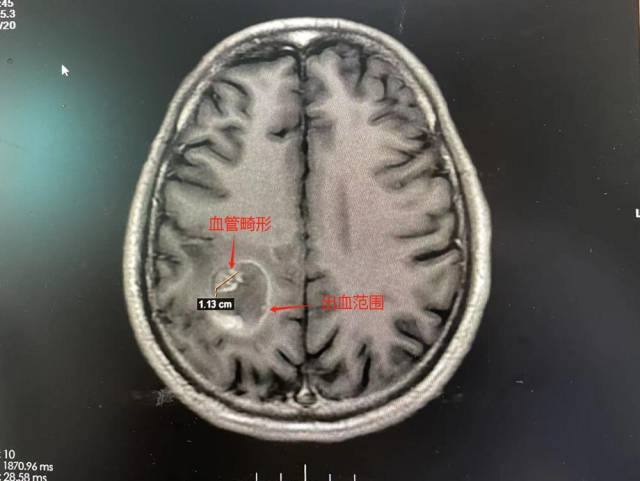

该院副院长、神经外二科主任林涛会诊时,结合影像检查结果,考虑患者右侧顶叶病灶为海绵状血管畸形合并亚急性期出血。经追问病史,周大爷今年5月就曾因摔跤后头晕在当地住院,当时CT检查提示颅内有一小团块白色病灶,怀疑是海绵状血管瘤破裂出血,经过保守治疗病情稳定后出院。

患者MR影像。 受访者供图

“病灶位于脑运动区,出血量大,已经形成明显占位效应,造成脑功能障碍。”林涛表示,如不行手术治疗,血肿持续压迫或增加,很可能会导致脑水肿加重,患者头晕、头痛、左侧肢体乏力会持续加重。